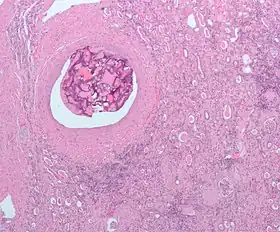

| Micrograph of the most common type of renal cell carcinoma (clear cell)—on right of the image; non-tumour kidney is on the left of the image. Nephrectomy specimen. H&E stain | |